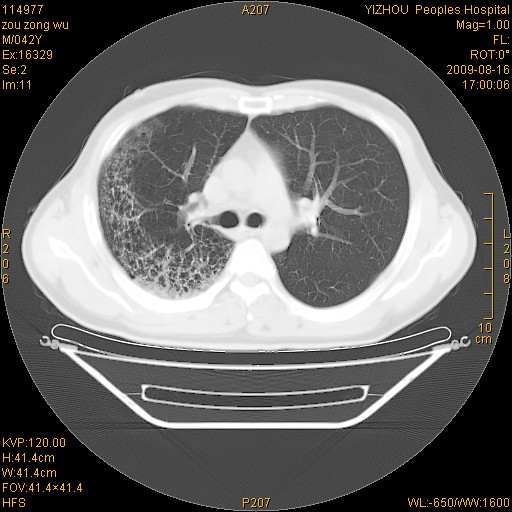

以下是引用zjzjr在2009-8-17 10:42:00的发言:[br]右侧间质性肺炎伴纤维化,右肺下叶肺囊肿伴感染(不除外外伤后引起),右肺野及胸壁软组织\\肝内见多发斑点状,中枪了吧.右侧胸膜肥厚\\粘连.